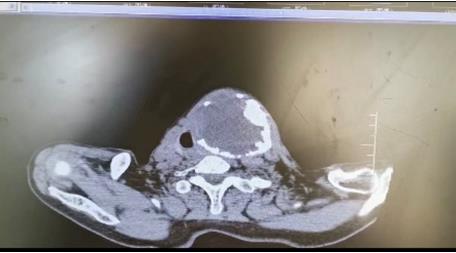

患者朱女士,68歲,頸部包塊呈進(jìn)行性增大50年,來院后彩超及CT提示左側(cè)甲狀腺腫瘤已經(jīng)超過10公分并邊緣鈣化,氣管移位較明顯,腫瘤較大屬于罕見,不僅給患者造成心理陰影,還影響了正常生活,偶有憋悶不適,進(jìn)食較大食物感哽咽不適。流動醫(yī)院下鄉(xiāng)義診時(shí),發(fā)現(xiàn)包塊已經(jīng)很大了,影響到頸部的活動及飲食。醫(yī)生與患者及家屬溝通講解病情,表示我們?nèi)揍t(yī)院能治療。最后患者及家屬抱著試一試的態(tài)度來到延安大學(xué)咸陽醫(yī)院。

因逐漸長大的頸部嚴(yán)重影響飲食及活動,長達(dá)50年的折磨,患者身體很瘦、體質(zhì)差。甲狀腺腫瘤,瘤體大,手術(shù)創(chuàng)面較大,損傷喉返神經(jīng)及甲狀旁腺風(fēng)險(xiǎn)高,術(shù)后可能出現(xiàn)聲音嘶啞及低鈣抽搐等嚴(yán)重并發(fā)癥。同時(shí)瘤體長期對氣管的壓迫,致術(shù)后可能出現(xiàn)氣管軟化而發(fā)生致命性并發(fā)癥。